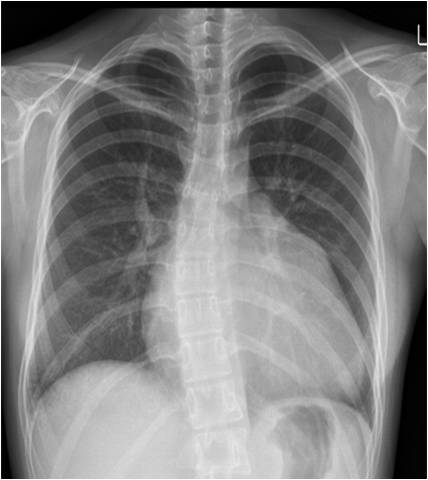

19 / M, Chief complaint: Recurrent episode of chest pain and cardiac enzyme elevation with normal coronary angiography, family history of sudden cardiac arrest

Jinwoo Son, Severance Hospital, Yonsei University College of Medicine